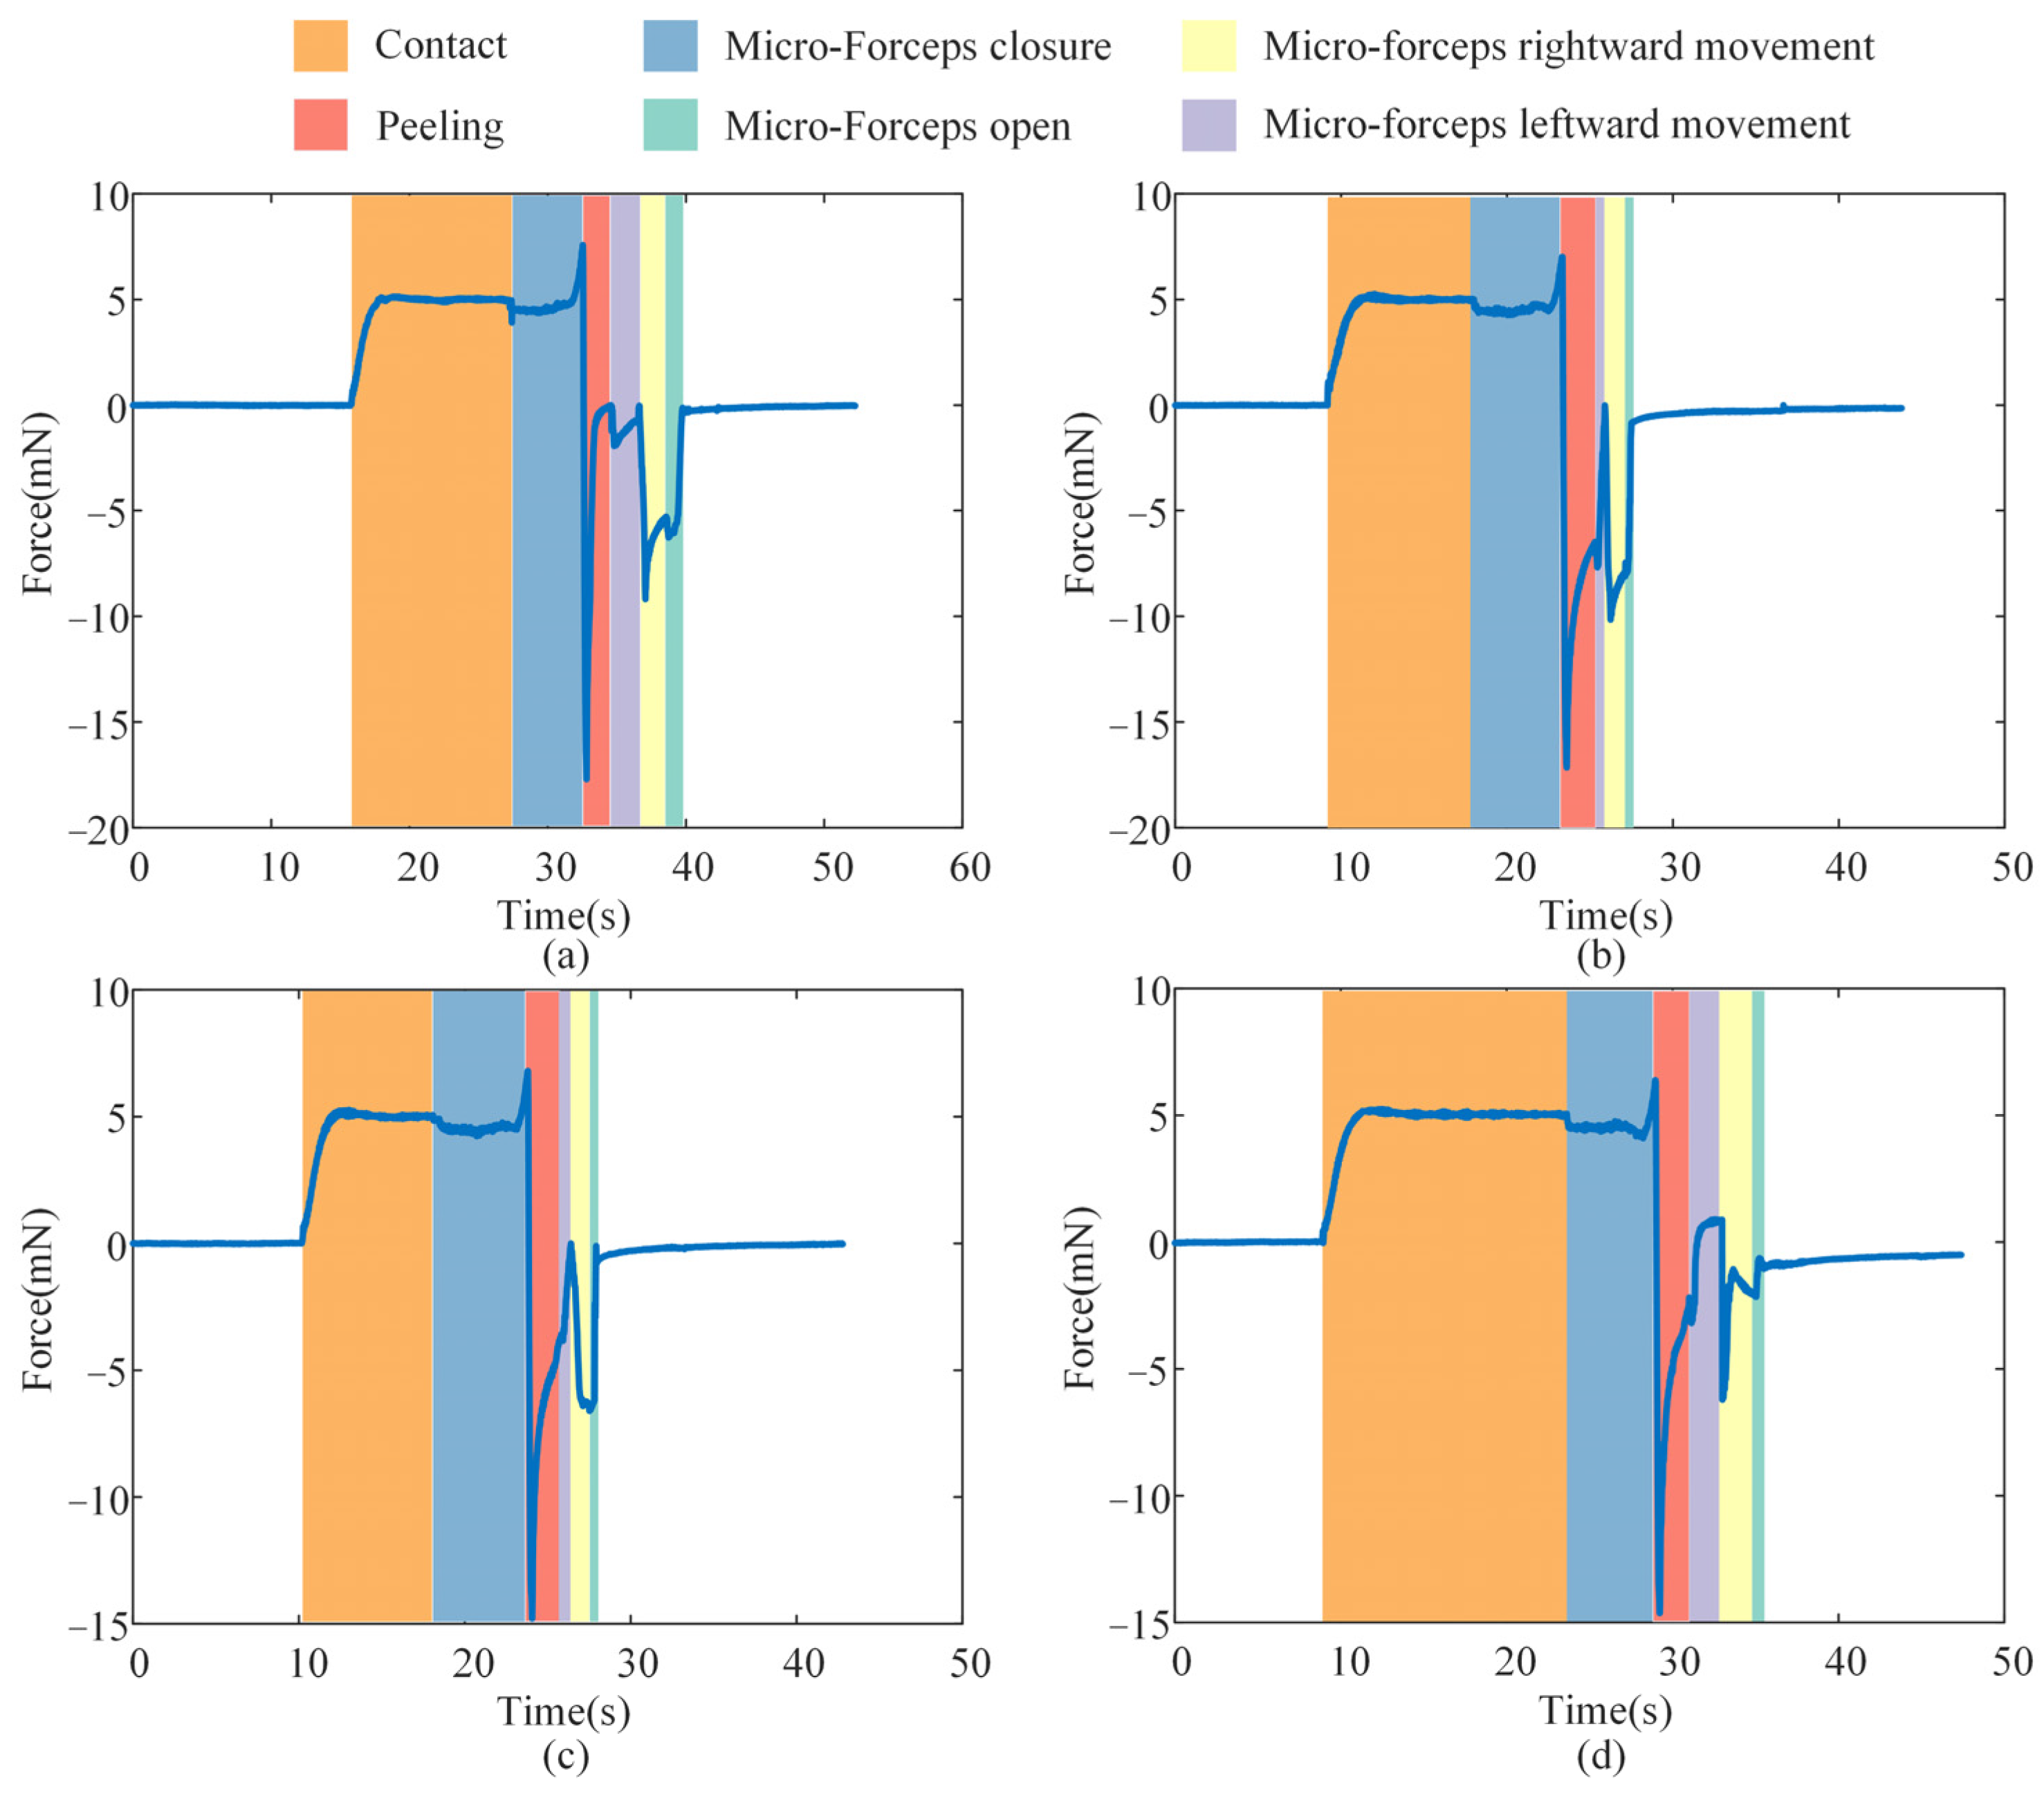

4.3. Break Initiation Experiment in ILM Peeling